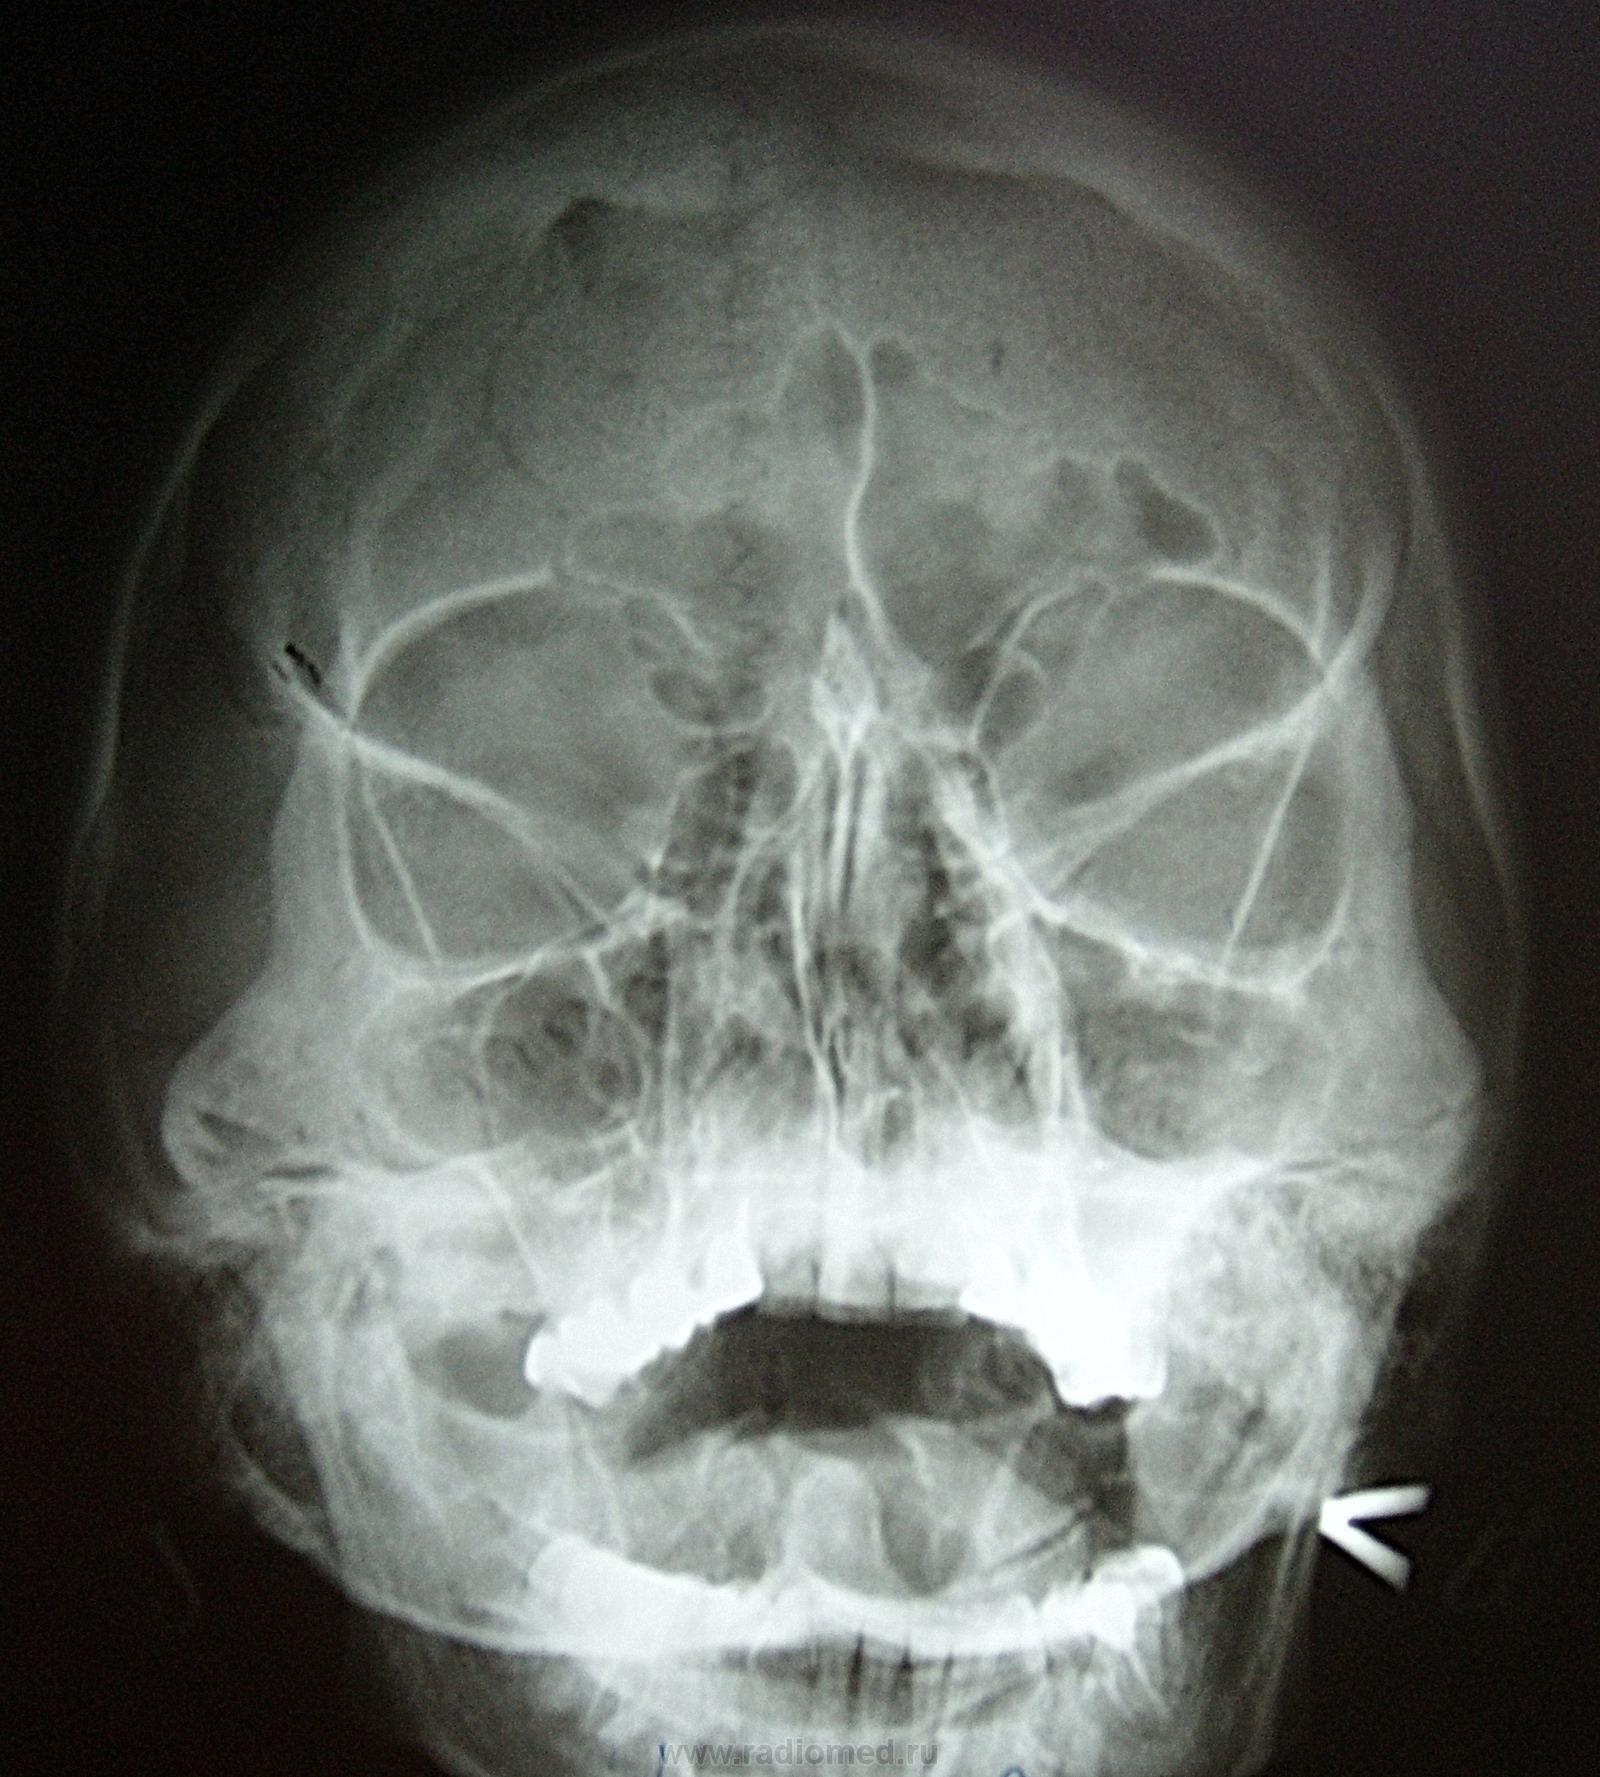

Пол пациента: Женский пол Тип патологии: Инфекция Область исследования: Скелетно-мышечная система Методы исследования: Rg Женщина была направлена отоларингологом для исключения гайморита. В прошло справа была операция по поводу экссудативного гайморита. Почему так истончена стенка справа? Это что , после пункции могло произойти? ID:12115 Wed, 16/02/2011 - 18:42 #1 Евгений1313 Offline Last seen: 13 years 1 month ago Joined: 15.10.2010 - 19:13 Posts: 808 Это стенка слева утолщена. Wed, 16/02/2011 - 21:46 #2 Almo Offline Last seen: 9 hours 24 min ago Joined: 28.09.2008 - 18:50 Posts: 8281 Я бы не сказал, что справа стенка истончена-норма. Wed, 16/02/2011 - 21:50 #3 Глазков Игорь А... Offline Last seen: 10 months 2 weeks ago Joined: 19.12.2008 - 20:41 Posts: 1597 за комментарии коллеги. Прийди к Себе Wed, 16/02/2011 - 21:56 #4 Леонид Offline Last seen: 9 years 1 month ago Joined: 13.01.2011 - 19:33 Posts: 445 Стенки околоносовых пазух должны быть: тонкими, чёткими, контрастными.

Это стенка слева утолщена.

Я бы не сказал, что справа стенка истончена-норма.

Стенки околоносовых пазух должны быть: тонкими, чёткими, контрастными.